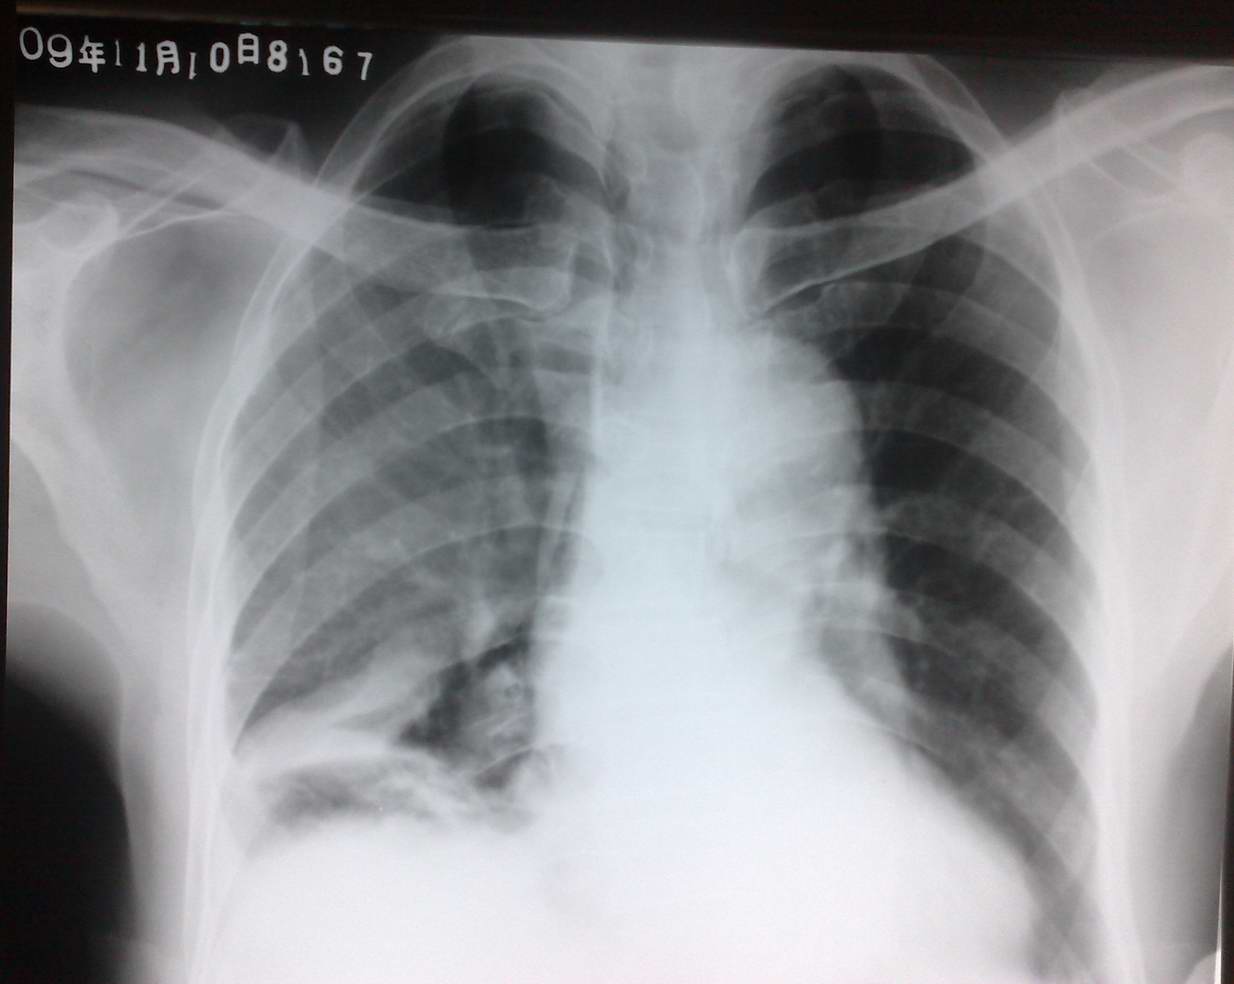

男性,74岁,反复咳嗽、咳痰、胸痛一个月,暂未发现其他不适。hbc:11.12x10的9次方, n:0.845,l:0.092,正常心电图。

用手机拍的,左膈面光滑,肋膈角锐利(未照出来),其余如片示。

wbc吧!wbc值1万1及中性粒升高提示细菌性感染。考虑右侧胸膜腔积液、叶间胸膜积液,右下盘状不张,临床及实验室提示合并右下感染。双肺透光度不对称可能是体位因素。建议ct排除占位性病变。

右肺下野见不规则片状阴影,右肺透光减弱,右侧膈肌升高,欠光滑,膈顶位于外三分之一。

诊断:右侧胸腔积液,肺底积液,叶间积液伴右肺下叶膨胀不全。